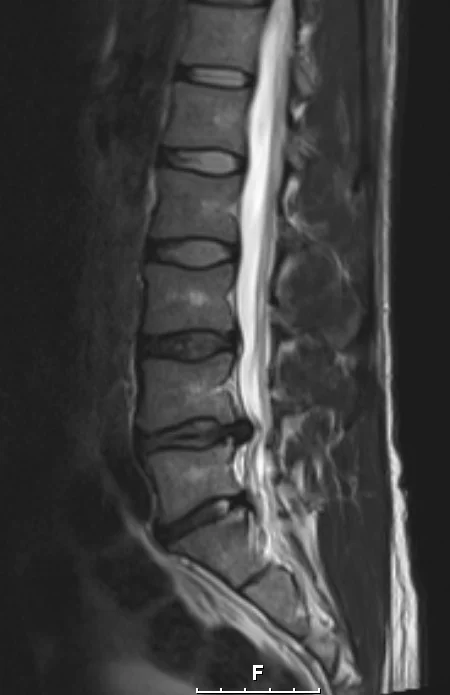

Eilisen tilanne magneetissa. Oikeasssa kankussa/lonkan seudulla ollut keväästä asti särkyä ulkokierrossa ja selällään on ollut vaikea maata. Tai oikeastaan mahdotonta niin että kankku ei olisi pienessä jännityksessä. Välillä kipu säteilee nilkkaan. Kuitenkin tuon kanssa on pystynyt elämään ja liikkumaankin kohtuullisesti.

Olen ollut sitä mieltä että kipu on lihasperäistä (tulehduksesta esim. ja liiasta autossa ja tuolilla istumisesta toimistotyöstä johtuen) ja olen sitä mieltä edelleen. Oikeastihan tuo pullistuma (joka on vasemmalla puolella) on kuvissa pahentunut, mutta vasemmalle puolelle ei kipua ole käytännössä ole ollut enää kevään jälkeen. Yksi selkä, yksi elämä. Kuvissa lokakuu 2012, maaliskuu 2013 ja joulukuu 2013.